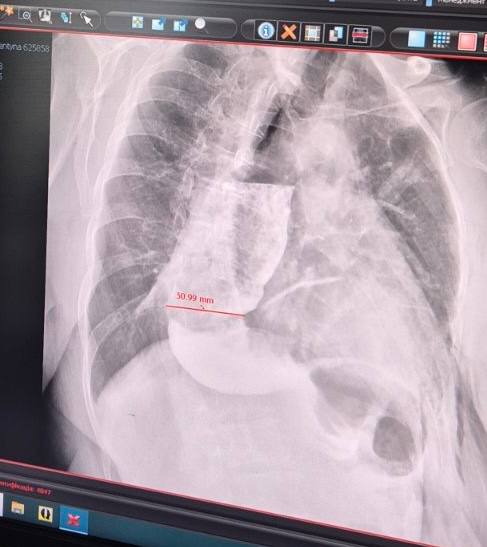

Медики діагностували у пані Валентини хворобу, яка зустрічається в 2 людей на 100 тисяч — ахалазію кардії стравоходу. Як розповіли лікарі, це розлад моторики травної системи, тобто клапан, через який їжа надходить у шлунок, спазмований і рефлекторно не відкривається. Їжа накопичується у стравоході і розтягує його. Норма для діаметру органу — до 3 сантиметрів, тоді як у Валентини він розтягнувся до семи.